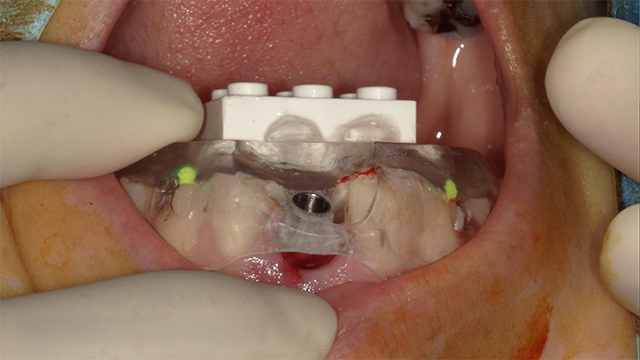

埋入において一番大切なのは“安全性”。志賀先生は、サージカルガイドを用いた埋入方法を推奨しています。

これにより、新人ドクターでも勤務3ヶ月目で埋入が可能になりますし、外科において重要なオペのスピードも術者の経験に左右されずに最短7分程度にまで縮めることが可能。

1mmのズレも起こさないために実は腕のある臨床家の先生ほどガイドを活用します。